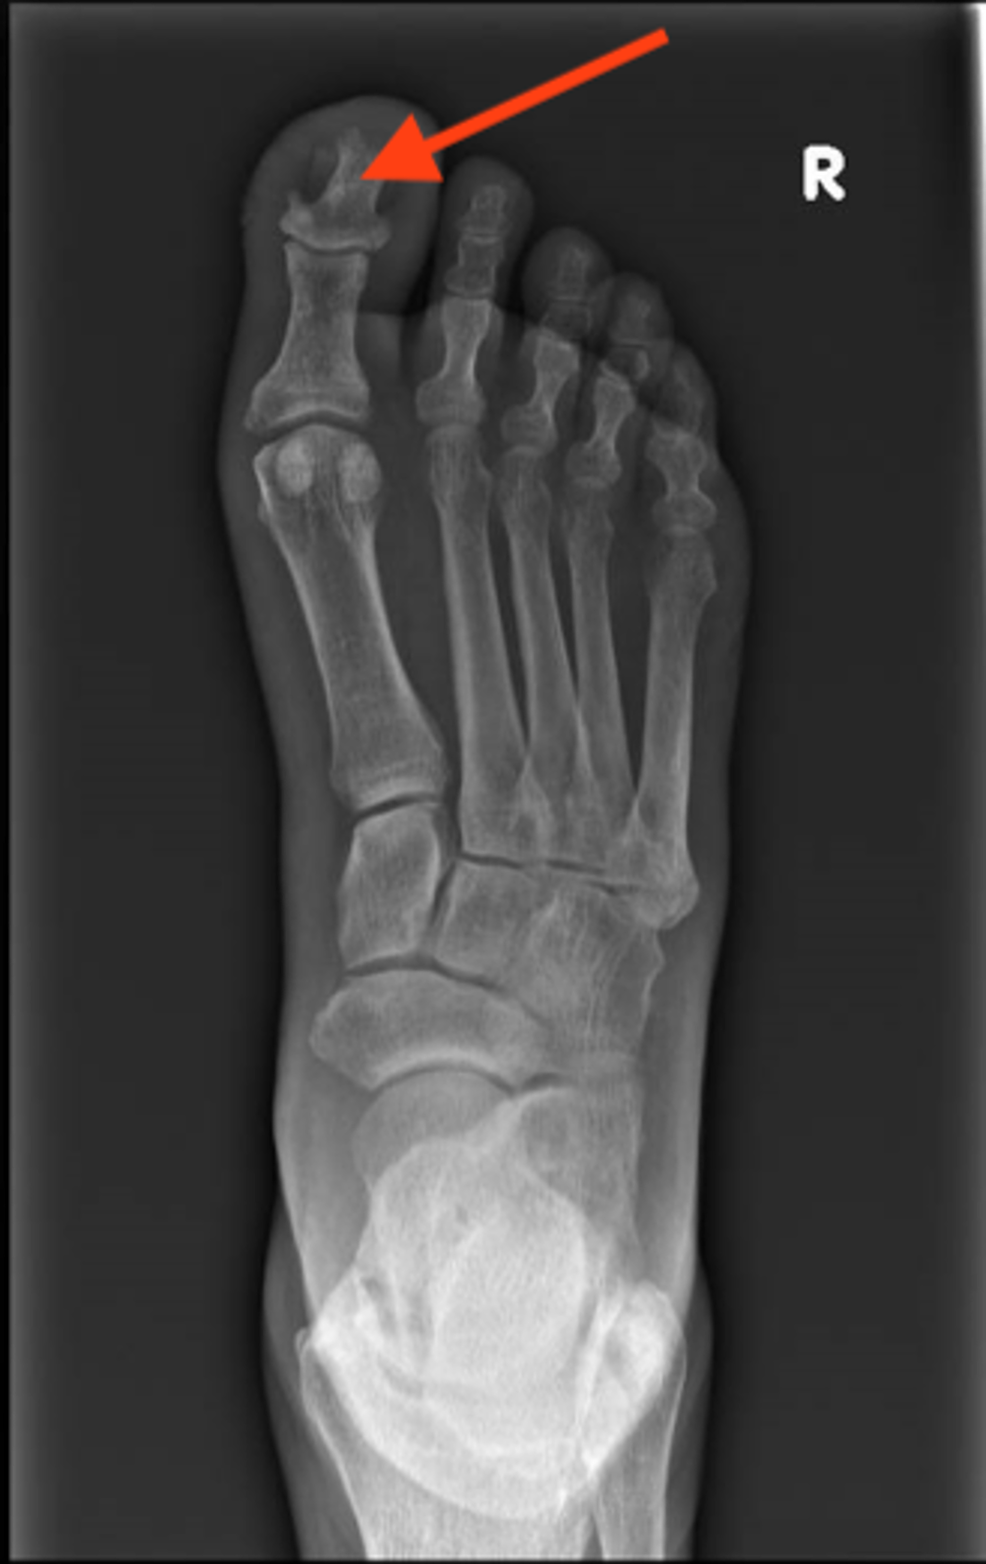

Erosion Of Distal Phalanx . Superficial acral fibromyxoma of the toe, with erosion of the distal phalanx. enchondromas are the most common primary bone tumour of the hand accounting for 62% to 85% of bone tumours in the. Many lcsions occur in the distal. 1) resorption of the terminal tuft (more. erosion of the distal phalanx. lesions of the distal phalanx may arise secondary to benign or malignant pathologies and may reflect primary or. distal phalangeal erosive lesions. Bakbara monsees and william a.

(PDF) Superficial acral fibromyxoma of the toe, with erosion of the Erosion Of Distal Phalanx Superficial acral fibromyxoma of the toe, with erosion of the distal phalanx. 1) resorption of the terminal tuft (more. erosion of the distal phalanx. distal phalangeal erosive lesions. enchondromas are the most common primary bone tumour of the hand accounting for 62% to 85% of bone tumours in the. Many lcsions occur in the distal. Bakbara monsees. Erosion Of Distal Phalanx.

Erosion of the distal phalanx beneath the epithelioid Erosion Of Distal Phalanx 1) resorption of the terminal tuft (more. erosion of the distal phalanx. distal phalangeal erosive lesions. lesions of the distal phalanx may arise secondary to benign or malignant pathologies and may reflect primary or. Many lcsions occur in the distal. Bakbara monsees and william a. Superficial acral fibromyxoma of the toe, with erosion of the distal phalanx.. Erosion Of Distal Phalanx.

Xray of the right foot (case no. 1) showing a radioluc Openi Erosion Of Distal Phalanx 1) resorption of the terminal tuft (more. erosion of the distal phalanx. Bakbara monsees and william a. enchondromas are the most common primary bone tumour of the hand accounting for 62% to 85% of bone tumours in the. distal phalangeal erosive lesions. lesions of the distal phalanx may arise secondary to benign or malignant pathologies and. Erosion Of Distal Phalanx.